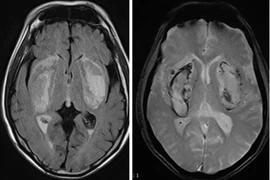

Trong gần 1 tháng qua, khoa cấp cứu BVĐK tỉnh Phú Thọ đã tiếp nhận 2 trường hợp ngộ độc nặng do dùng phải cồn giả pha nước để uống. Tình trạng nguy kịch do methanol đang gia tăng người dân cần biết cách phòng tránh.